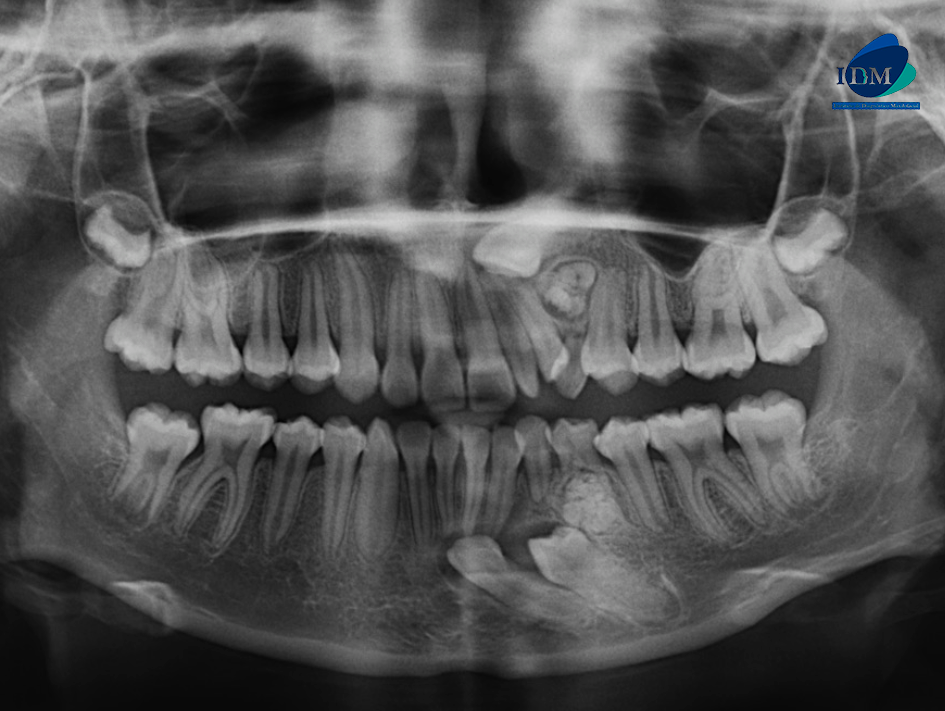

Paciente femenino de 13 años de edad, es referido al Instituto de Diagnóstico Maxilofacial – IDM para evaluación general.

En la radiografía panorámica (Figura 1), se aprecia mineralización parcial del proceso estilohiodeo izquierdo, neumatización alveolar de senos maxilares, imagen radiopaca circunscrita de un halo radiolúcido proyectada entre los segmentos radiculares de piezas 22 – 24 y tercio medio radicular de pieza 74.

Radiografia Panorámica